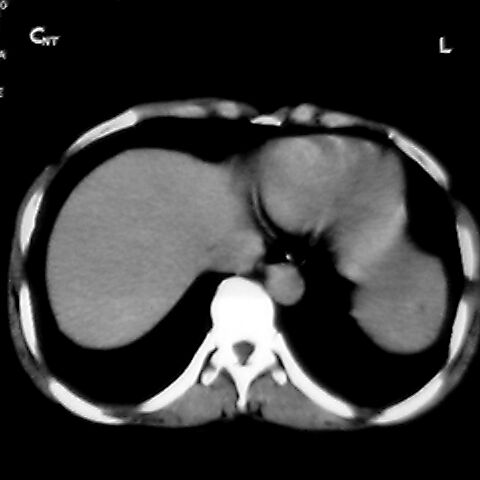

女 48岁 食道癌术前体检发现脾占位。

脾胀内部巨大低密度肿块,边界清或不清,中心坏死,轻度增强,内见散在钙化,结合食道癌病史多考虑:转移癌.

1肝右下叶小囊肿2右肾上极囊肿或错构瘤3脾脏不典型血管瘤可能性大.

脾脏低密度灶伴钙化,增强化明显,中心见液化坏死灶,强化延时明显。考虑血管瘤。转移瘤待排。

右肾见类圆形低密度影.结合病史.脾及右肾转移性ca可能性大

1,脾血管瘤。2,右肝,右肾小囊肿。